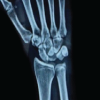

A 36-year-old man, clerk by occupation, came to orthopedic outpatient depart in B.K.L. Walawalkar rural medical college and hospital Dervan in May 2019 with complaints of difficulty in performing right (dominant hand) ringer finger movements for the past 3–4 months. Formation of fist was associated with a clunk in palm and, pain and heaviness in radial side of hand, that is, the thumb, index, middle finger, and ring finger. Opening of fist relieved all the symptoms. He had no history of trauma and no comorbidities. On clinical examination, there was triggering of the right ring finger at palm. No obvious swelling was noted. There was no wasting of thenar eminence. In extension on deep palpation, a firm swelling was palpable in palm along the ring finger which moved proximally along the flexor tendon of ring finger and disappeared on flexing the ring finger. In this position, the patient developed pain and heaviness along the radial three fingers. Tinel’s sign was positive only in this position. Phalen’s test was negative. Transillumination test was negative. In X-ray, no abnormality was noted. Ultrasound showed a well-defined hypoechoic partially compressible focal oval lesion, measuring 19 × mm in size with no vascularity inside, and arising from FDP of the right ring finger, located just distal to palmer aponeurosis. This swelling moved longitudinally along the FDP of ring finger during flexion and extension of ring finger. Median nerve was normal. These findings were suggestive of lipoma/giant cell tumor of FDP tendon of ring finger. After counseling, pre-operative and pre-anesthetic check-up patient was posted for excision of the lump. Regional block was given and tourniquet used. An ulnar palmar approach of AO was chosen for this as it facilitated easy exposure of FDP tendon of ring finger as well as distally same could be used to do carpal tunnel release (Fig. 1, 2, 3, 4).

At 2 years follow-up, the patient was clinically and radiologically assessed (Fig. 6). He was completely asymptomatic and performing all his activities without any discomfort or limitations of wrist or fingers. There was no triggering and USG confirmed no recurrence of fibrolipoma.